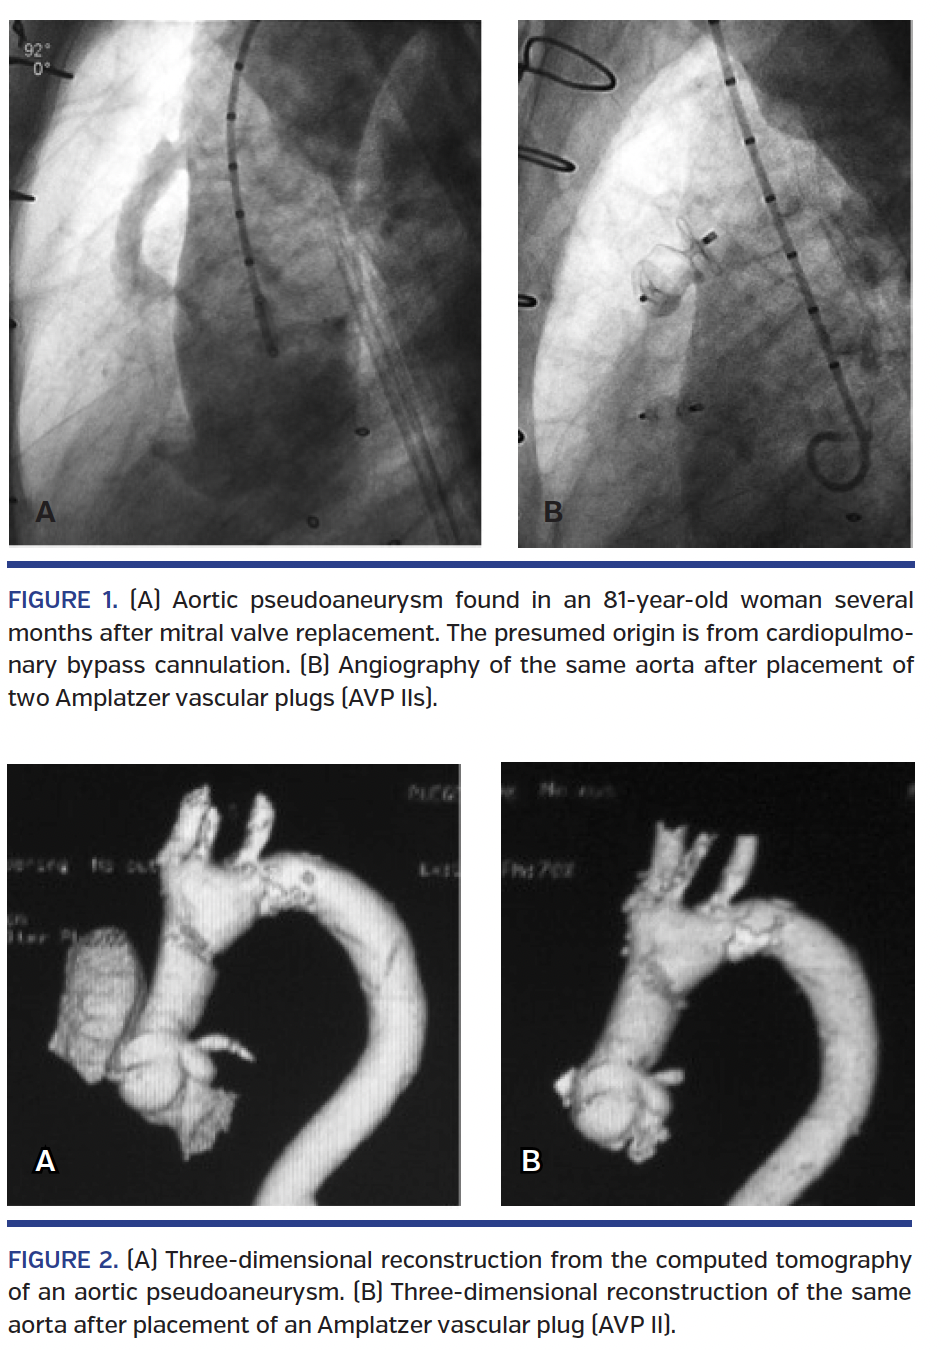

Patients. Subjects ranged in age from 22-80 years. All of our patients experienced APSAs as a result of a prior cardiac surgery. Previous surgeries included aortic root replacement (n = 2), ascending aortic graft placement (n = 4), and descending thoracic aortic repair (n = 2), with additional APSAs occurring at the cannula insertion site for cardiopulmonary bypass (n = 2) (Figure 1A). In 4 patients, the initial aortic insult was an aortic dissection. APSAs varied in location from as proximal as the aortic root to as distal as the descending thoracic aorta. Three patients had an APSA in the ascending aorta adjacent to the right coronary artery ostium.

All patients were initially diagnosed using CTA. Five patients were diagnosed incidentally on routine postoperative surveillance (Figure 2A), 3 patients presented with symptoms of chest or epigastric pain, 1 patient experienced dyspnea and was found to have a concomitant aortic paravalvular leak that was treated at the time of APSA repair, and 1 patient presented with non-specific symptoms of fatigue. APSA size, as assessed by CTA, ranged between 6 mm (anterior-posterior) x 4 mm (transverse) x 12 mm (longitudinal) and 45 mm x 67 mm x 79 mm. In 1 patient, an APSA originating at the non-coronary sinus of Valsalva was found to be compressing the ascending aorta, although this patient remained asymptomatic.

Procedural outcomes. The procedure was well tolerated by all 10 patients. No hemodynamically or electrically significant events occurred. AVPs ranging in size from 6-16 mm were deployed in 6 patients. Four of these patients required two AVPs each due to multiple APSA connections with the aortic lumen, and 1 patient received four AVP IV devices — two each during two separate interventions. Two patients received ASOs (6 mm and 10 mm) and 1 patient received an 18 mm Amplatzer patent foramen ovale occluder (this patient was presented in a previous case report).18

Proper device deployment was confirmed in 8 out of 10 patients intraprocedurally via TEE, ICE/ILE, or aortography (Figures 1B and 2B). In 1 patient, both ICE and aortography were unable to confirm proper device placement. This patient, early in our experience, had aortography that failed to reveal the defect, highlighting the challenges of imaging for this condition. This patient underwent a postprocedure magnetic resonance image that showed improper device placement within the false lumen of a dissected ascending aneurysm. Within 1 week, the patient was taken back for a repeat attempt at percutaneous repair, which was successful under ICE guidance. In another patient, two AVP IV devices were placed in two separate pseudoaneurysms, with an apparently successful result by angiography and TEE. However, CTA revealed two additional defects, which were subsequently closed with two more AVP IV devices using ICE guidance.